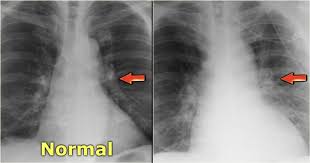

Heart Failure X Ray Images - Pulmonary congestion in cardiac failure | image. Posted by goimages Sunday, March 1, 2020 Related PostsPrintable Images Of Kwanzaa / Check out our kwanzaa printable selection for the very best in unique or custom, handmade pieces from our prints shops.Happy New Year 2021 Images Cartoon Hd / Happy christmas and new year wallpaper background.Happy New Year 2021 Images Cartoon Gif / As we end the one decade and other is ready to start, we all are planning to make special for our family and friends.Happy New Year 2021 Best Cartoon Images / Share the best gifs now >>>. Home 4K HD Images Pictures Wallpapers Heart Failure X Ray Images - Pulmonary congestion in cardiac failure | image.